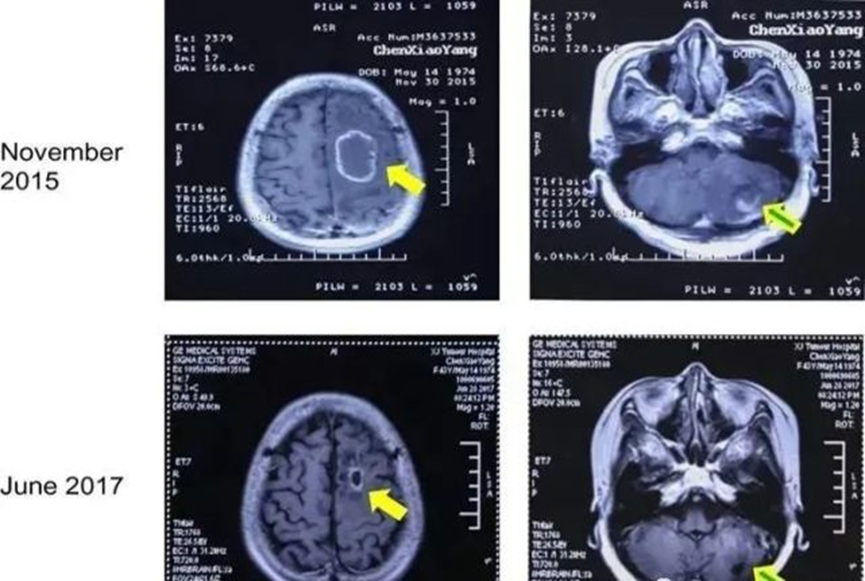

图(2)案例1:吸氢治疗前后头部脑后MRI